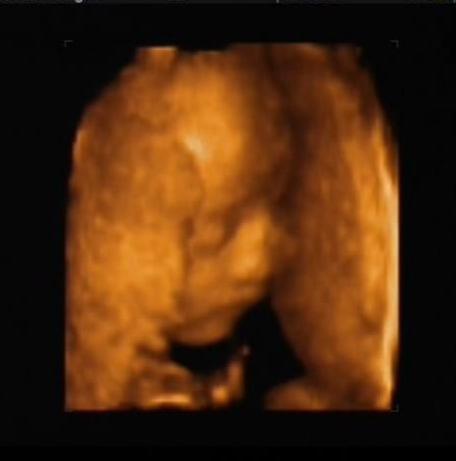

Persze nehogy azt higyjétek, hogy élvezte a kukucskálást. Megmutatta a lényeget, de aztán elfordult, eltakarta magát... Nem is akárhogy!!!

Na, mostmár elegem van... (két kézzel takarja az arcát)